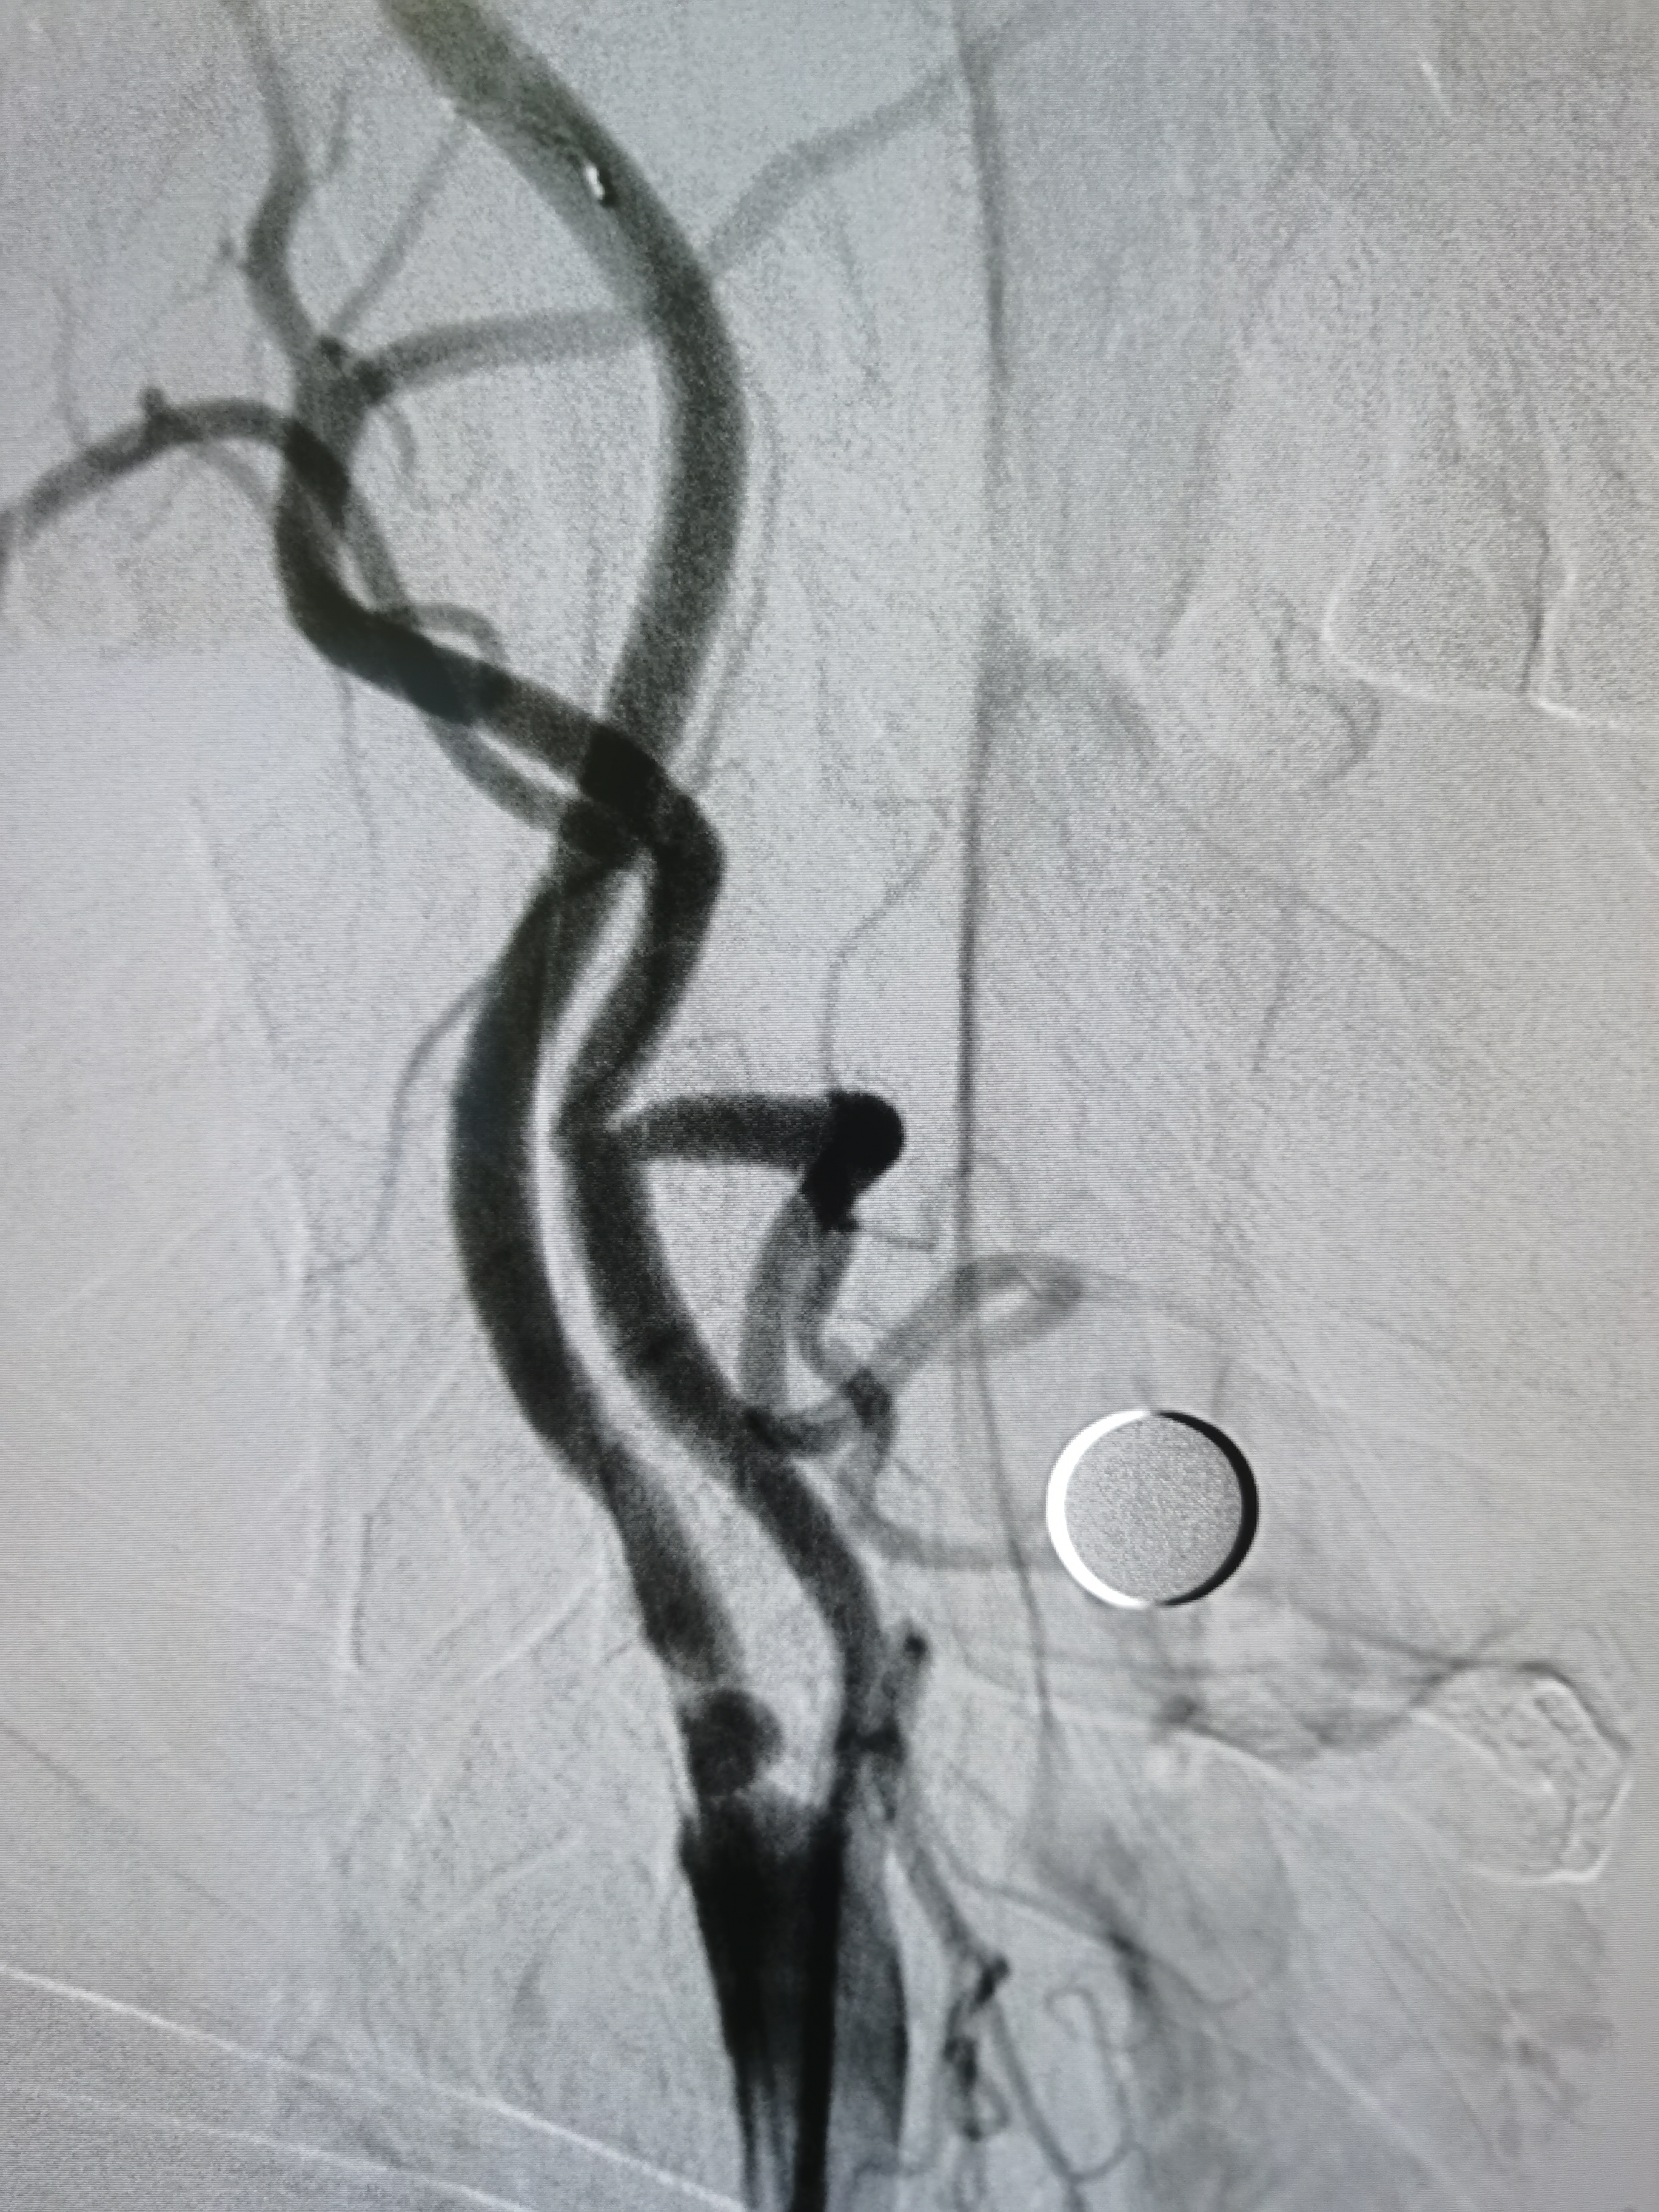

左侧颈内动脉狭窄伴溃疡形成。

将导引导管调至左侧颈总动脉末端,远端置入保护伞。

9/30支架定位。

支架释放后狭窄改善,覆盖不稳定斑块。

支架释放后颅内血供良好。

颅内血供良好。